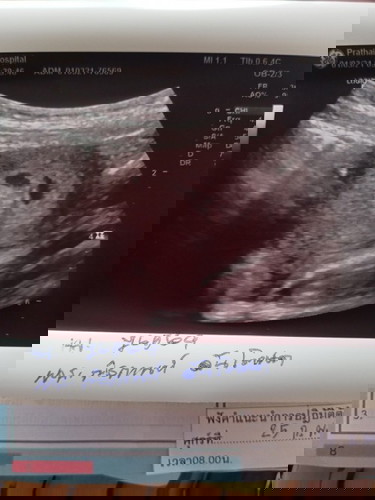

วันนี้หนูไปอัลตร้าซาวด์ซ้ำตามที่หมอนัดคลำไม่พบแล้วยังซาวด์ไม่เจอตัวอ่อนเหมือนเดิมค่ะ แล้วหมอบอกว่าพบ2แซ็กคืออะไรคะ แล้วตอนพบหมอก่อนกลับบ้านหมอบอกแค่ว่าอย่าพึ่งทำอะไรนะแค่นี้ค่ะหนูกังวลใจมากๆเลยค่ะคือหนูไม่รู้จะทำยังไงต่อแล้วแต่ว่าหมอห้องจ่ายยาหมอบอกให้บำรุงเยอะๆดื่มนมมากๆ อีก2สัปดาห์มาอัลตร้าซาวด์ใหม่ค่ะ😥😥#ขอคำแนะนำหน่อยค่ะ #ท้องแรกคะ #ขอบคุณล่วงหน้านะคะ

เจอถุงตั้งครรภ์2ถุง แต่ยังไม่เจอไข่แดงหรือตัวอ่อน ช่วงนี้คุณแม่ต้องระวังมากๆนะคะ แล้วก็บำรุงเยอะๆค่ะ ของเราก็มีถุงตั้งครรภ์2ถุง แต่เจอไข่แดง 1ถุง แล้วอีก1 สัปดาห์ไปซาวด์ใหม่ เจอน้อง มา2 เลยค่ะ เป็นกำลังใจให้ค่ะ😍😍

ท้องยังอ่อนอยู่ค่ะ จะเห็นแค่ถุงตั้งครรภ์นะคะ บางคนเห็นตอน10wไปแล้วก็มีค่ะ แต่ถ้าซาวด์ผ่านช่องคลอดจะเห็นชัดเลยค่ะ ละเอียดด้วย ยินดีกับคุณแม่น้องแฝดด้วยนะคะ